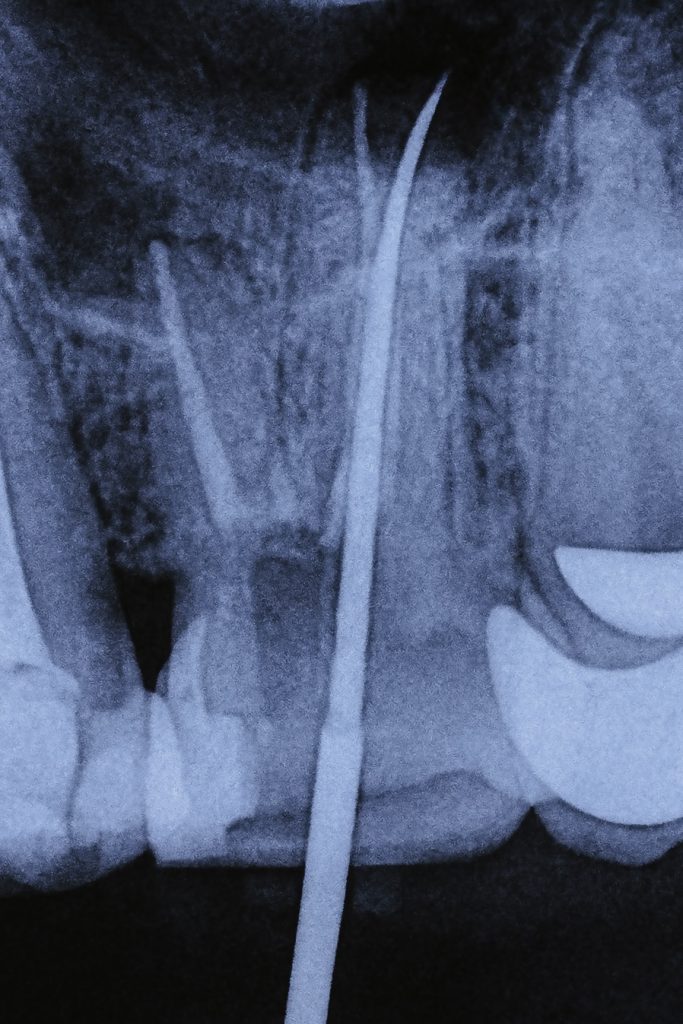

- Rotary NiTi system was used for shaping; irrigants included 5.25 % NaOCl and 17 % EDTA, both sonically activated for effective disinfection. (Fig 3–4)

Obturation was performed using bioceramic sealer with warm vertical compaction, ensuring a dense, continuous fill into the palatal split and accessory canals. Post-operative radiograph confirmed ideal obturation and apical control. (Fig 7)

- Radiographically: Perfect obturation of the palatal split with bioceramic sealer and uniform adaptation.